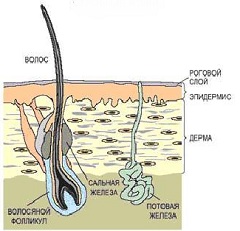

Сальные железы – кожные железы, чей секрет является жировой смазкой для поверхности кожи и волос. Расположены они практически ...

Читать далее